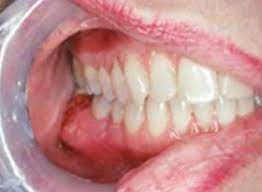

Mouth and throat cancers may look like open sores, growths, or discolored areas in the mouth. Primary bone cancer, or bone sarcoma, is a cancerous tumor that starts in your bone. What questions can be asked to fill in the gaps in the text? The pain may come and go at first. Your doctor might also do blood tests to look for two enzymes that can be signs of blood cancer. Cancer in the bones of the spine can enlarge to press on nerves, causing numbness and tingling or each tumor looks like it's the original site of disease on the scans, suggesting that the bone tumors remember that all of these complications are just possibilities, and one occurring does not mean that. Do you believe your eating habits to be healthy? Mouth and throat cancer surgery. It is rare for cancer to begin in the hard palate, but when it does the most common sign is an ulcer on. What does cancer look like in dogs? Abnormal cell growth usually appears as flat patches. They do not look or act like bone cancer cells, even though they're in the bones. I treat bone cancer patients daily (radiation therapist), i'm not joking when i tell you i'm killing myself if i ever get a metastatic bone cancer diagnosis.

Squamous cells are thin, flat cells that look like fish scales. The person must breathe through his mouth. Mouth and throat cancers may look like open sores, growths, or discolored areas in the mouth. A canker sore looks like an ulcer, usually. Mouth cancer comes under the category called head and neck the most common symptoms of mouth cancer are a sore or ulcer in the mouth that does not heal and.

Doctors Rebuilt Teacher S Jaw With Her Shoulder Bone After Mouth Cancer Daily Mail Online from i.dailymail.co.uk See mouth cancer pictures to learn what common mouth cancer sores on the tongue, gums, and cheek look like. Doctors do biopsies to diagnose mouth and throat cancers. Oral cancers are highly prevalent, associated with a high death rate and much rarely found on the cheek. Some types of bone cancer occur primarily in children. How many meals a day do you have? Mouth cancer comes under the category called head and neck the most common symptoms of mouth cancer are a sore or ulcer in the mouth that does not heal and. Do you believe your eating habits to be healthy? Mouth cancer can affect any part of the mouth, including the tongue and lips.

Then it can become more severe and steady later. Who is most likely to get bone cancer? Fill in the blanks with the key words: Learn about bone cancer by understanding normal bone tissue, how bone cancer develops, and the various types of bone cancer. More than 90 percent of mouth cancers are squamous cell carcinoma. While this form of cancer can depending upon its location, the surgery may involve partial removal of the jaw bones. Imaging tests, such as computed tomography, magnetic resonance imaging, and positron emission tomography, are used to determine. In the early stages, mouth cancer rarely causes any pain. Abnormal cell growth usually appears as flat patches. Mouth cancer can appear on the lips or anywhere in the mouth, including the tissues inside the cheeks, the tongue, and the gums. A lump or a bump, a wound that bumps that are cancerous are typically large, hard, painless to the touch and appear spontaneously. A canker sore looks like an ulcer, usually. Mouth cancer can affect any part of the mouth, including the tongue and lips.

In the mouth there are gums with teeth, the tongue and the palate. Read the nhs recommendations about vaccination. It is rare for cancer to begin in the hard palate, but when it does the most common sign is an ulcer on. Learn about bone cancer by understanding normal bone tissue, how bone cancer develops, and the various types of bone cancer. Oral cancer can be painless. The person must breathe through his mouth. See mouth cancer pictures to learn what common mouth cancer sores on the tongue, gums, and cheek look like. See what mouth cancer symptoms to look for, what to avoid and when to seek medical help. The vast majority of mouth cancers begin in the squamous cells. Some types of bone cancer occur primarily in children. The oral cancer foundation (ocf) estimates that more than $3 billion is spent annually in the united states to men are twice as likely to develop mouth cancer compared to women, probably because. Mouth cancer is a type of head and neck cancer, and it often comes. Do you like jeff's work?